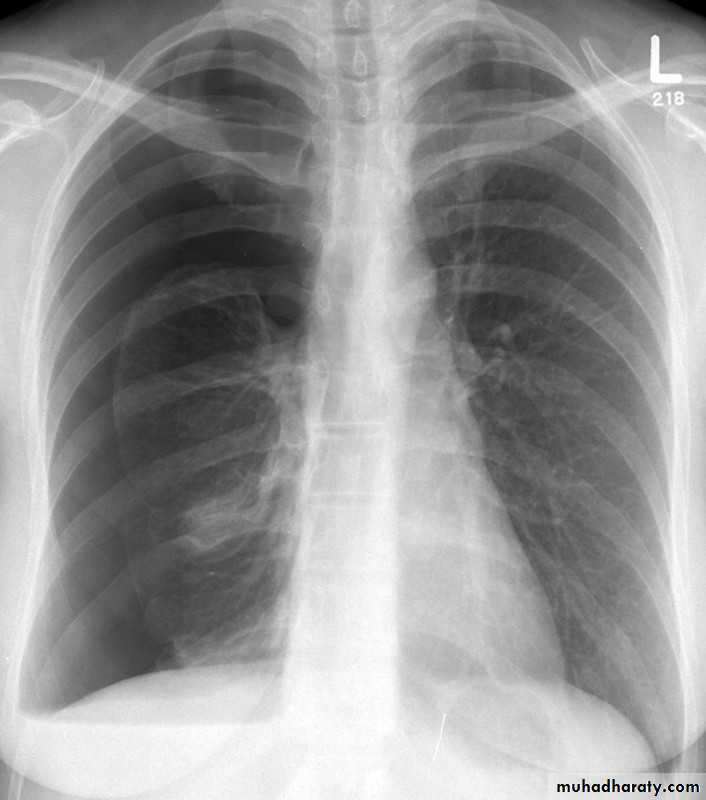

NORMAL PA view